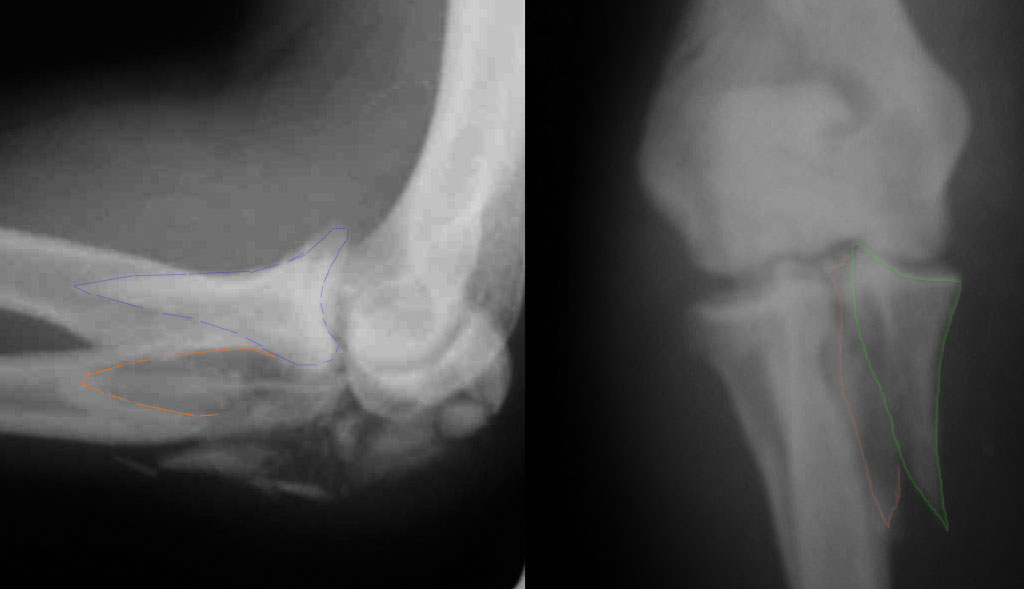

Прикрепляю снимок, где обведен фрагмент, несущий на себе венечный отросток (весь он смещён с этим фрагментом или частично - без качественной боковой проекции судить сложно), и отдельно на снимке обведено "ложе", от которого он сместился.

Почему я в данном случае против Вебера (хотя обычно горячий сторонник)? Да потому, что спицам нередко не хватает жёсткости, чтобы удержать предплечье от волярного подвывиха. При таком оскольчатом переломе спицы порой просто "прогибаются" за счёт одного только натяжения проволочной петли и головка луча может уйти в волярный подвывих (может, конечно, и не уйти). Но я бы предпочёл фиксировать всё к жёсткой пластине (включая фрагмент с венечным отростком) и, по возможности, исключить послеоперационную внешнюю иммобилизацию. Накладывать на такой локоть после операции гипс -- означает обрекать его на тяжёлую контрактуру.

Головка луча, кстати, на мой взгляд цела.